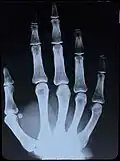

X-Ray image of right hand with no details in the bones at the bottom of the image -

Original: X-Ray image of right Hand;

1st. order equidensities after pseudo-solarization of original -

colored 1st. order equidensity-series using pseudo-solarization, B&W copies chromogenic developed